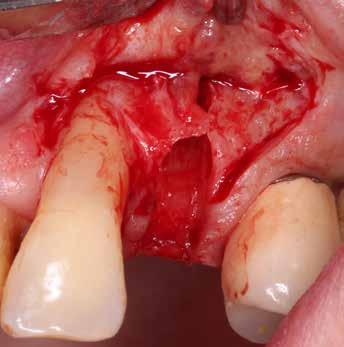

A korai harmicas éveiben járó hölgy rendelőnkbe érkezésének oka a jobb felső nagymetsző fog bizonytalan érzkenysége, elmondása alapján gyermekkorában trauma érte a felső frontrégiót. A frakturált klinikai koronákat kompozittöméssel helyreállították, egyéb kezelést akkor nem tartottak szükségesnek. Az utóbbi hónapokban tapasztalt érzékenység miatt kereste fel rendelőnket. A klinikai vizsgálat (1. és 2. kép) és a CBCT felvétel (3. kép) alapján diagnosztizált külső gyökérreszorpció megoldására a fog eltávolítását, implantátum

bukkális 1. kép: Kiindulási állapot, 2020. január. 3. kép: Kiindulási CBCT felvétel. 2. kép: Kiindulási állapot a palatinális oldal felől.

falat mint „pajzsot”, meg kell őrizni, ezzel megelőzhető a bukkális csontfal egyébként fiziológiás reszorpciója (4. és 5. kép). A sebészi technika különös körültekintést követel meg, nehogy a bukkális „gyökérpajzs” megmozduljon, ezzel a bukkális oldalon megmaradt periodontális ligamentumok sérülését kockáztatnánk, amely az esetenként